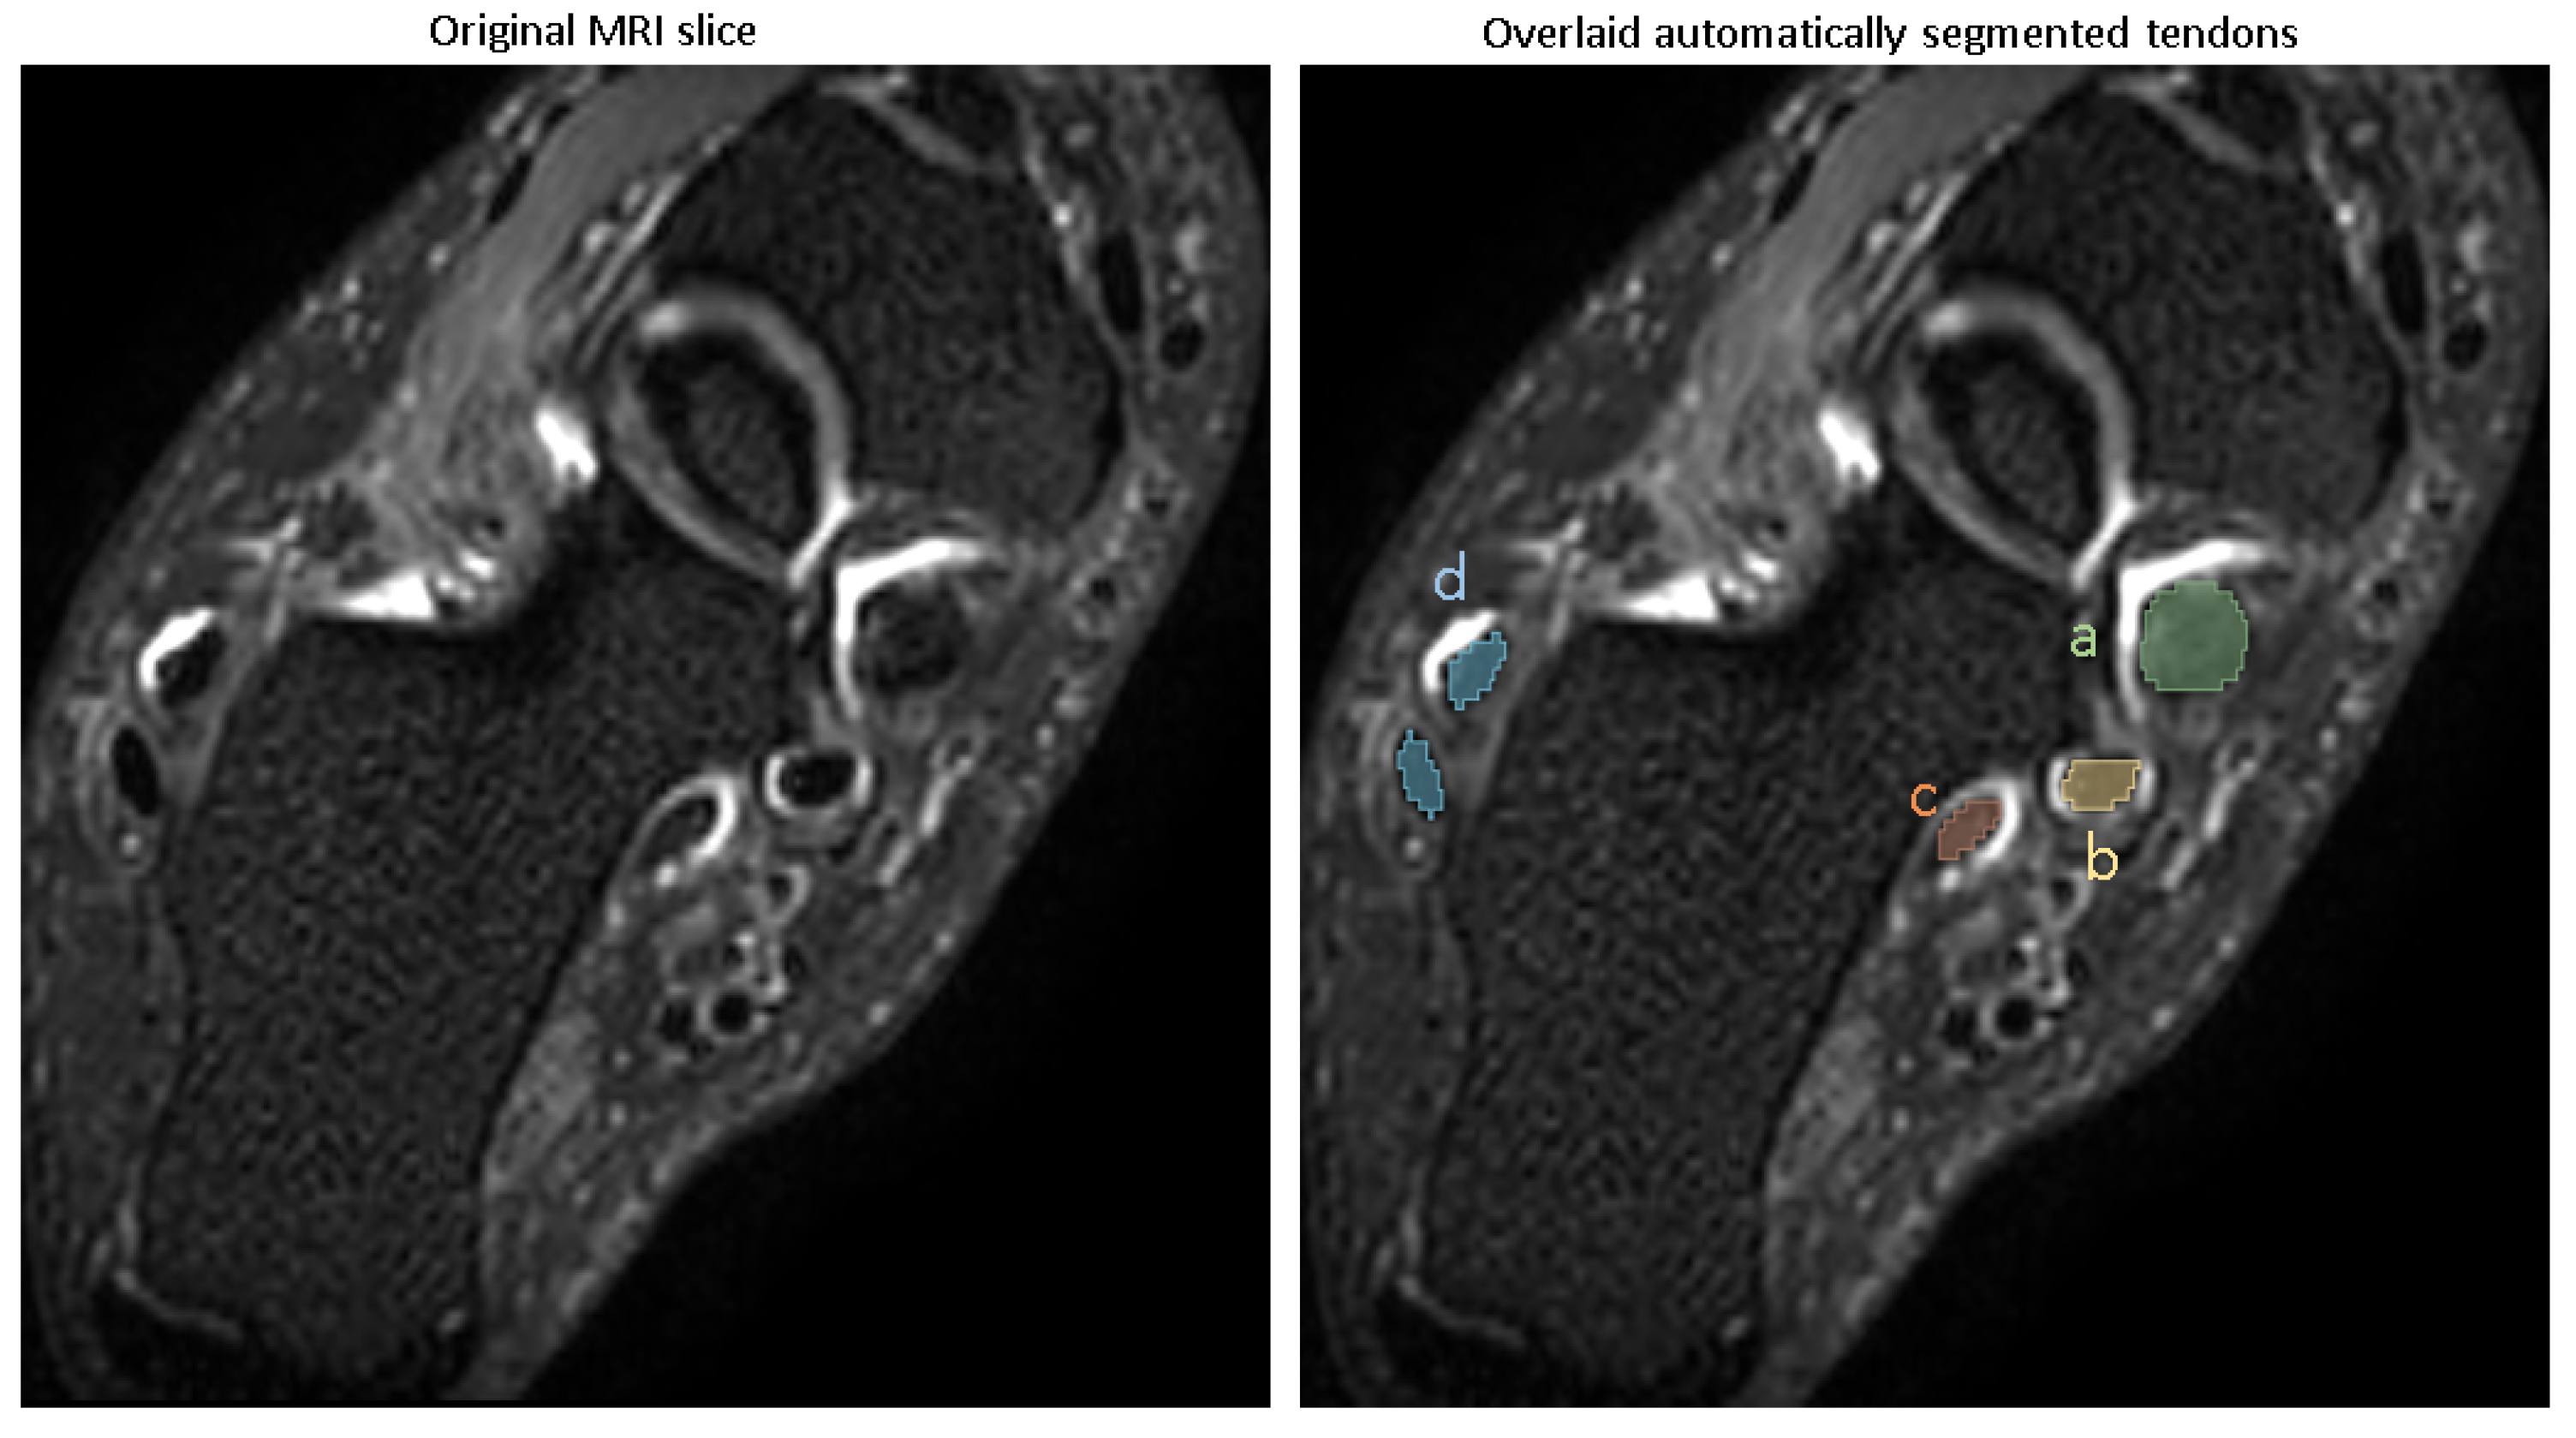

The visual examples of the results of the automatic pathology segmentations for an image are depicted in Figure 4.

The trained models were used for predicting pathologies in the test set, and the Dice scores reported the similarity of the predicted segmentation with the ground truth segmentation. The accuracy of segmentation in terms of Dice score (mean ± SD) is shown in Table 2, with all pathologies showing mean Dice scores of >0.8.

These Dice scores indicate that the models are capable of reliably segmenting tenosynovitis pathologies in the ankle across different regions, with high overlap compared to expert-validated reference segmentations.

Figure 4. Example image overlaid with automatic segmentation of 4 tenosynovitis pathologies. (a) Tibialis posterior tenosynovitis (score: 3), (b) flexor digitorum tenosynovitis (score: 1), (c) flexor halluces longus tenosynovitis (score: 1), (d) peroneal longus/brevis tenosynovitis (score: 1).